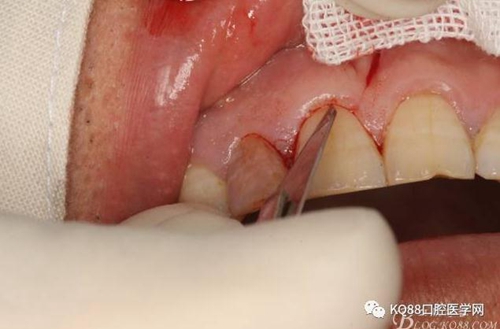

圖6.行唇側(cè)角形切口(11近中垂直切口+齦溝內(nèi)水平切口)垂直切口距離前庭溝約1~2mm。這樣可以減輕術(shù)后腫脹。

圖7. 角形切口中的齦溝內(nèi)切口情況:11號刀片伸進齦溝內(nèi)斜切。